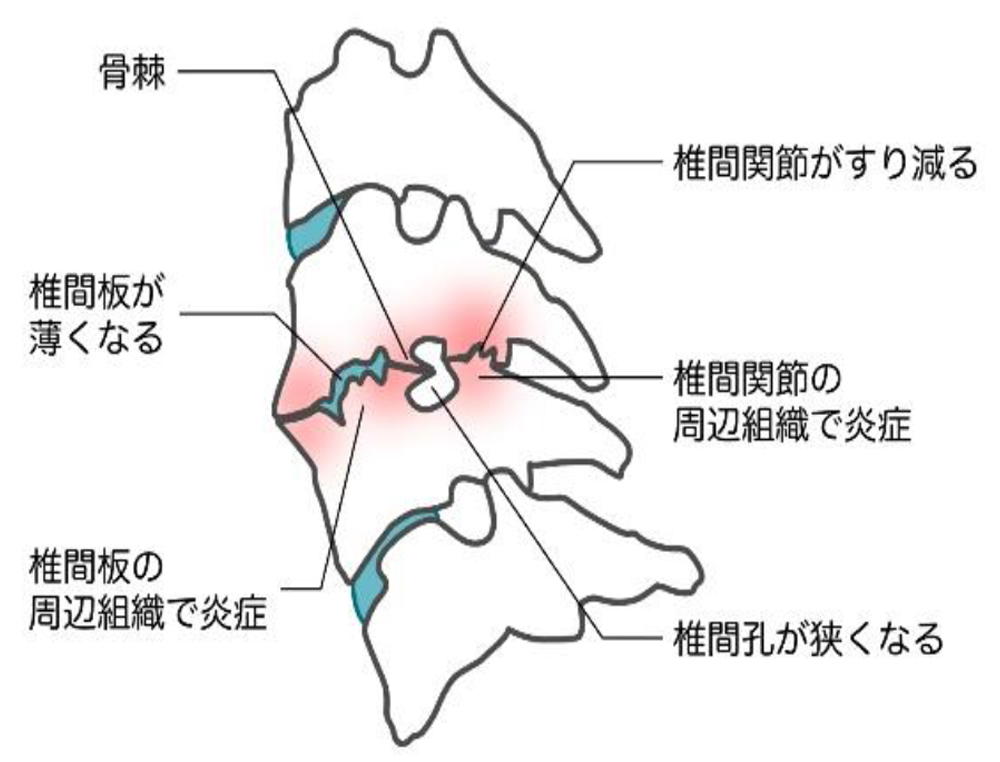

■頸椎症(変形性頸椎症)

首の骨(頸椎)に負担がかかり続けることで、頸椎の関節・椎間板、そしてその周囲の筋肉や靭帯に損傷が累積して、首の痛みや張り・コリなどの症状が出現する疾患です。

■原因③ 老化

椎骨と椎骨の間でクッションの働きをする椎間板は、老化によって水分が減少していきます。これにより、衝撃をうまく緩和できず、痛みが生じることがあります。

加齢による椎間板の変性が進み、骨がとげ状に大きくなって骨棘を形成することや、靭帯が厚く硬くなることで脊柱管にある脊髄が圧迫され、四肢に痛み、しびれが出る疾患です。